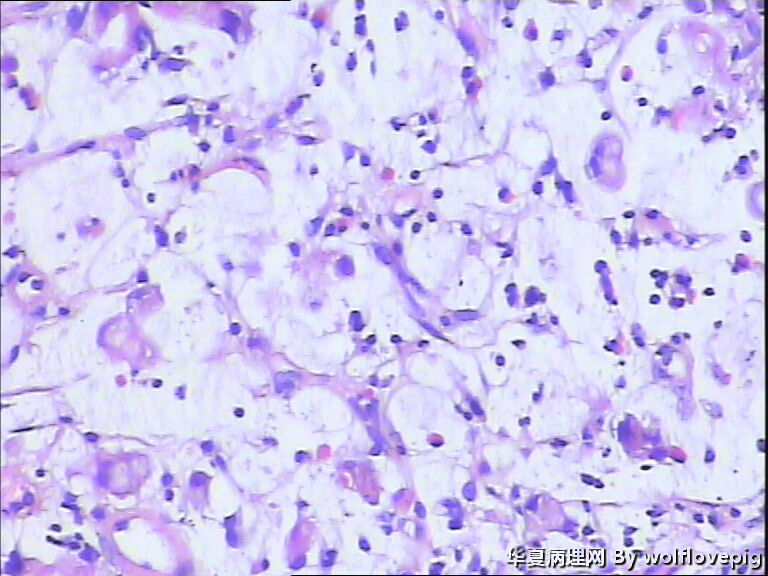

男,60y,胃窦呈结节样改变。

图1